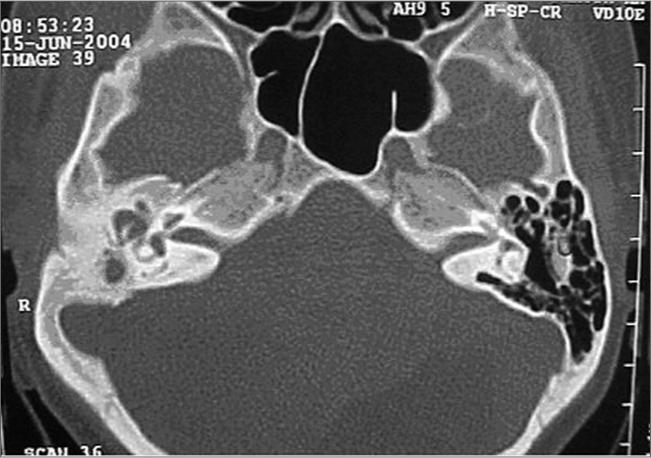

Middle ear papilloma.

Braz J Otorhinolaryngol. 2007 May-Jun;73(3):431. doi: 10.1016/s1808-8694(15)30092-6.

https://cdn.ncbi.nlm.nih.gov/pmc/blobs/2872/9445732/ace508c248a4/gr1.jpg